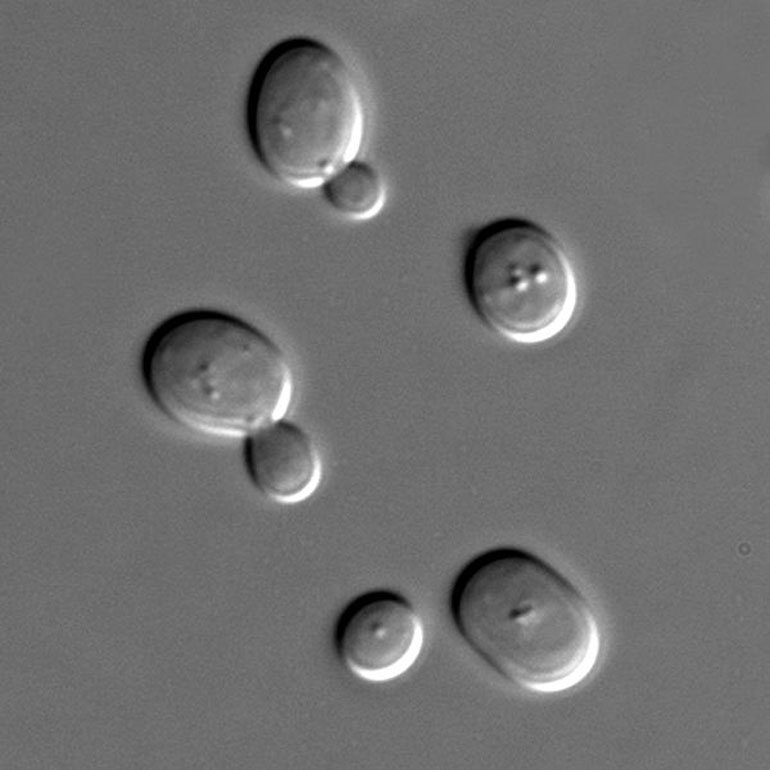

Επιστήμονες στη Βρετανία τροποποίησαν γενετικά το κύτταρο του ζυμομύκητα (της γνωστής μαγιάς), εισάγοντας σε αυτό άλλα γονίδια μύκητα. Με τον τρόπο αυτόν, ο ζυμομύκητας παρήγαγε μόρια της πενικιλίνης, του γνωστού αντιβιοτικού.

Όμως, η τροποποίηση «εξωτικών» μικροοργανισμών, οι οποίοι έχουν πολύτιμες αντιβακτηριακές ιδιότητες, δεν είναι καθόλου εύκολη υπόθεση για τους συνθετικούς βιολόγους. Αντίθετα, ο πασίγνωστος ζυμομύκητας (μαγιά) είναι πανεύκολο να μεταλλαχθεί κατάλληλα, μέσω της εισαγωγής DNA από άλλους μύκητες και βακτήρια.